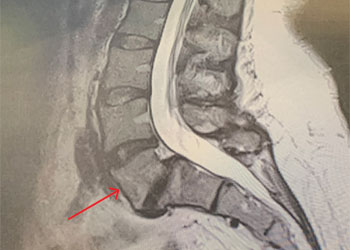

Spine:

Thoracic Spinal Cord Tumor Case Presentation

Author: Xavier P. J. Gaudin D.O., F.A.C.O.S., Read More!